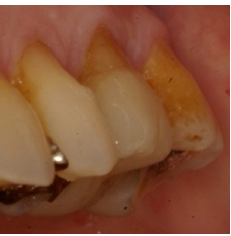

Preparación dentaria en #36 para EC. Un chamfer fue realizado en la pared vestibular.

EC en #36 después de 18 años (IPS-Empress). Obsérvense las facetas de desgaste parafuncionales, la recesión gingival y la lesión cervical no-cariosa. Esta paciente se negó a usar placa de estabilización nocturna.